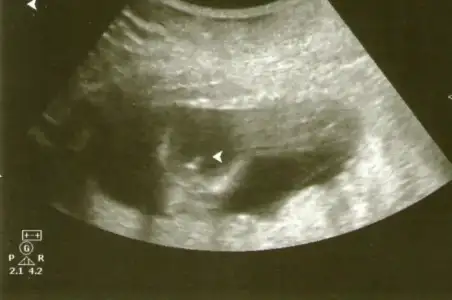

Selamm.. Bende 12 Haftalık Gebeyim. Bebeğimin Resmini Ekliyorum, Nub Teorisine Göre Kıza Benzettim Ben Ama Sizde Yorumlayabilir Misiniz? Teşekkürler.

$ghjlk.webp :nazar: